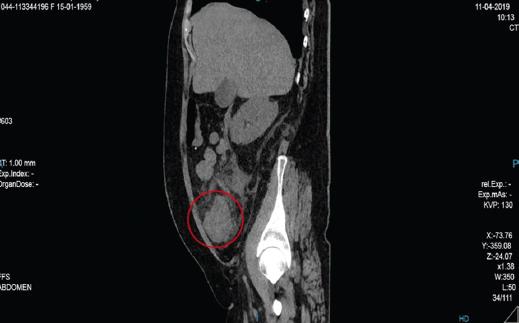

Mujer de 60 años, con antecedentes de diabetes tipo 2 e hipertensión arterial sistémica; niega antecedentes quirúrgicos. Inicia su padecimiento actual un día antes de su valoración con dolor de tipo cólico en el hipocondrio derecho, de intensidad 7/10 en la escala numérica del dolor, irradiado al cuadrante inferior derecho, acompañado de distensión abdominal, náusea llegando al vómito de contenido gastroalimentario en tres ocasiones, sin exacerbantes ni atenuantes; de manera ocasional, en las últimas 12 horas se presentó con dolor de tipo punzante, de intensidad 10/10 en la escala numérica del dolor, en la región de la fosa iliaca derecha. En la exploración física, neurológicamente íntegra, cardiopulmonar sin compromiso, abdomen globoso a expensas de panículo adiposo, peristalsis aumentada en intensidad y frecuencia, doloroso a la palpación en hipocondrio derecho y fosa iliaca derecha, Murphy negativo, McBurney positivo, con presencia de masa palpable en la fosa iliaca derecha, de aproximadamente 5 × 5 cm, móvil, no adherida a planos profundos y de consistencia firme; resto sin alteraciones. Laboratorios: leucocitos 12.67 103/μl, hemoglobina 14.1 g/dl, hematocrito 44.2 %, plaquetas 367,103/mm3, neutrófilos 82%, glucosa 24.2 mg/dl, urea 32.4 mg/dl, BUN 15.0 mg/dl, creatinina 1.0 mg/dl, sodio 137.0 mmol/l, potasio 4.6 mmol/l, cloro 98.8 mmol/l, bilirrubina total 0.18 mg/dl, bilirrubina directa 0.44 mg/dl, bilirrubina indirecta 0.26 mg/dl, DHL 357 U/l, AST 15.5 U/l, ALT 10.5 U/l, fosfatasa alcalina 107 U/l, ACE 2.13 ng/ml, C1-125 87.2 U/ml y AFP 3.54 U/ml. Tomografía abdominal en fase simple: imagen sugestiva de apendicitis aguda retrocecal complicada, con acentuados cambios inflamatorios y líquido libre en hueco pélvico, con engrosamiento nodular de la pared del ciego con múltiples ganglios ileocecales y retroperitoneales (paraórticos, intercavoaórticos y retrocrurales), el mayor de 17 mm, que pudieran ser por el proceso inflamatorio por contigüidad sin poder descartar una lesión subyacente del colon (Figs. 1 y 2). Se decide su tratamiento quirúrgico abierto, durante el cual se encuentra una tumoración a nivel de ciego y colon ascendente, de aproximadamente 10 cm, de consistencia firme, con tejido inflamatorio, y perforación a nivel de tercio medio, con salida de material fecal a la cavidad, así como proceso agudo en fase II a nivel apendicular. Se realizan hemicolectomía derecha e ileostomía, y se envía la pieza a patología. Se coloca drenaje de tipo laminar de media pulgada dirigido al hueco pélvico, el cual emerge a nivel del cuadrante inferior derecho (Figs. 3 y 4).

Figura 2 Tomografía abdominal en fase simple, corte transversal, en la que se aprecia una tumoración aparentemente dependiente del ciego (círculo).